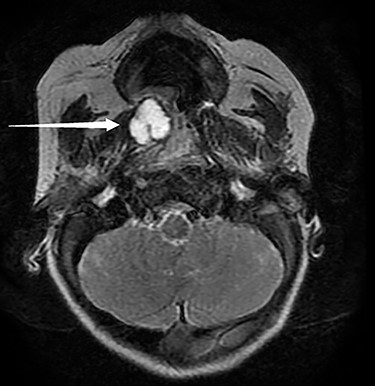

The patient was hospitalized for respiratory difficulty. During his hospitalization, the patient had episodic desaturations down to 65%, which were improved minimally with suctioning and repositioning. While asleep, the patient developed intermittent increased work of breathing, nasal flaring, subcostal and suprasternal retractions which necessitated increased respiratory support and ICU placement. Inpatient magnetic resonance imaging (MRI) exhibited a 1.6 × 1.4 × 1.5-cm right-sided cystic submucosal mass arising from soft palate with no aggressive features or invasion (Fig. 1).

Pictured is an MRI displaying a 1.6 × 1.4 × 1.5-cm cystic submucosal mass arising from the right soft palate.